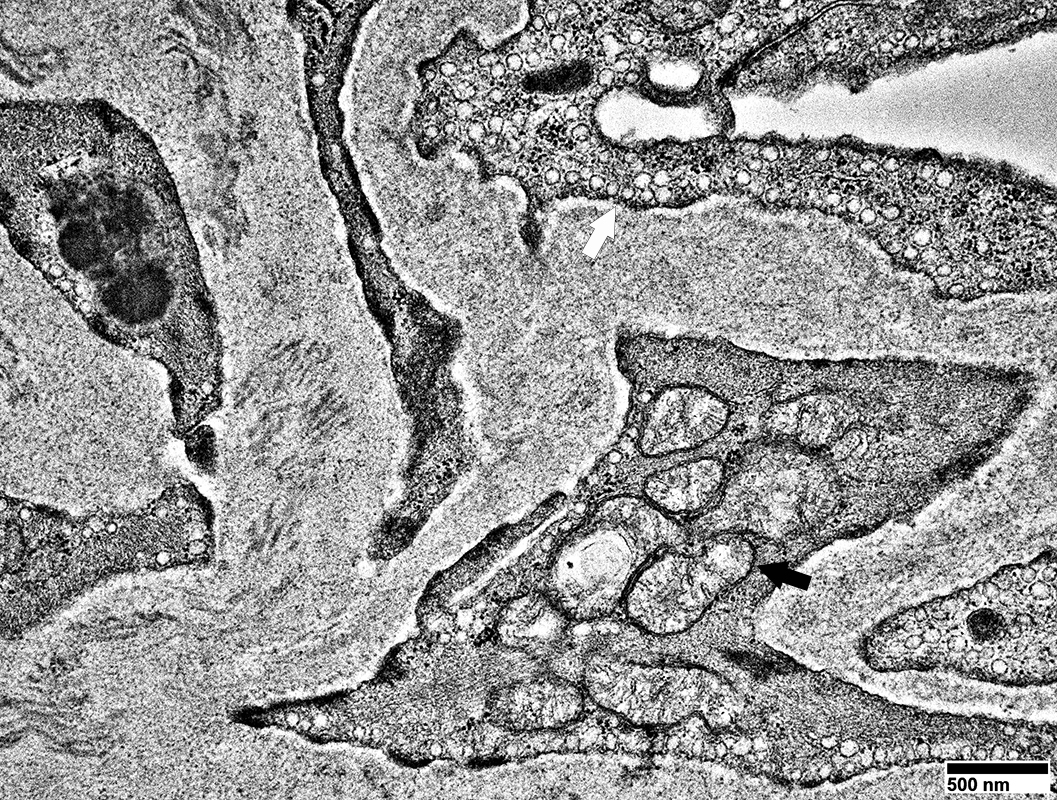

Pericytes   Mitochondrial proliferation & enlargement (Black arrows)

Endothelial cells   Multiple small vacuoles (White arrows)

From: R Schmidt